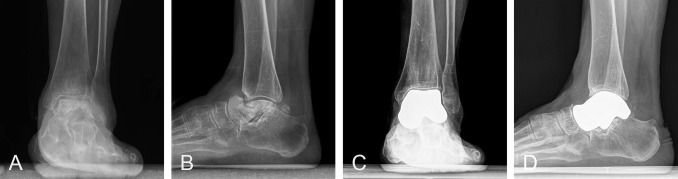

Standing anteroposterior (AP) and lateral radiographs of a 63-year-old female patient with primary avascular necrosis of the talus.

The team performed total talus replacements (TTR) in 39 patients suffering from either primary or post-traumatic AVN, following them for an average of two years. The results were incredible. According to the surgeons, pain levels dropped from an average of 8.2 out of 10 before surgery to just 2.1 afterward. Ankle mobility nearly doubled, from roughly 50° to over 95°. And over 90% of patients said they were “very satisfied and would undergo the procedure again.”